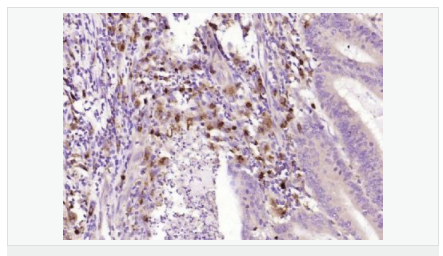

產(chǎn)品應(yīng)用WB=1:500-2000 ELISA=1:5000-10000 IHC-P=1:100-500 IHC-F=1:100-500 ICC=1:100-500 IF=1:100-500 (石蠟切片需做抗原修復(fù))

免 疫 原KLH conjugated synthetic peptide derived from human Sepiapterin reductase:101-200/261